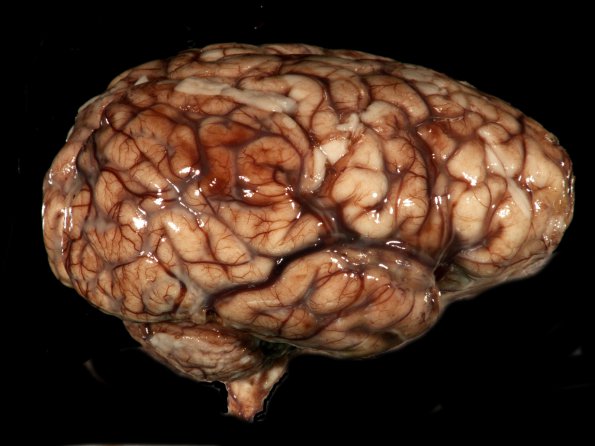

Washington University Experience | INFECTION | Bacteria | Meningitis | Meningitis, acute | 9A1 Meningitis, GBStrep (Case 7) Gross_7

There is little purulent material along the lateral aspect of the cerebral hemispheres, even in a close-up (#9A2).